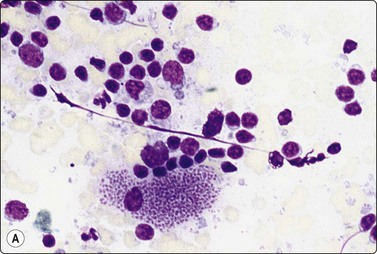

image image image

Fig. 18.19 Filariasis due to Dirofilaria repens

(A) With multiple microfilariae in background of neutrophils, with blunt heads and tapered rear ends (insert) (Pap, ×200); (B) Aggregated eggs (Pap, ×400); (C) Adult gravid female in background of eosinophils, from FNB of ‘malignant’ breast lesion (Pap, ×200).

(Figures 19A, 19B Courtesy Dr Khosrow Daneshbod, Shiraz, Iran; Figure 19C Courtesy Dr Roy, Mumbai, India)